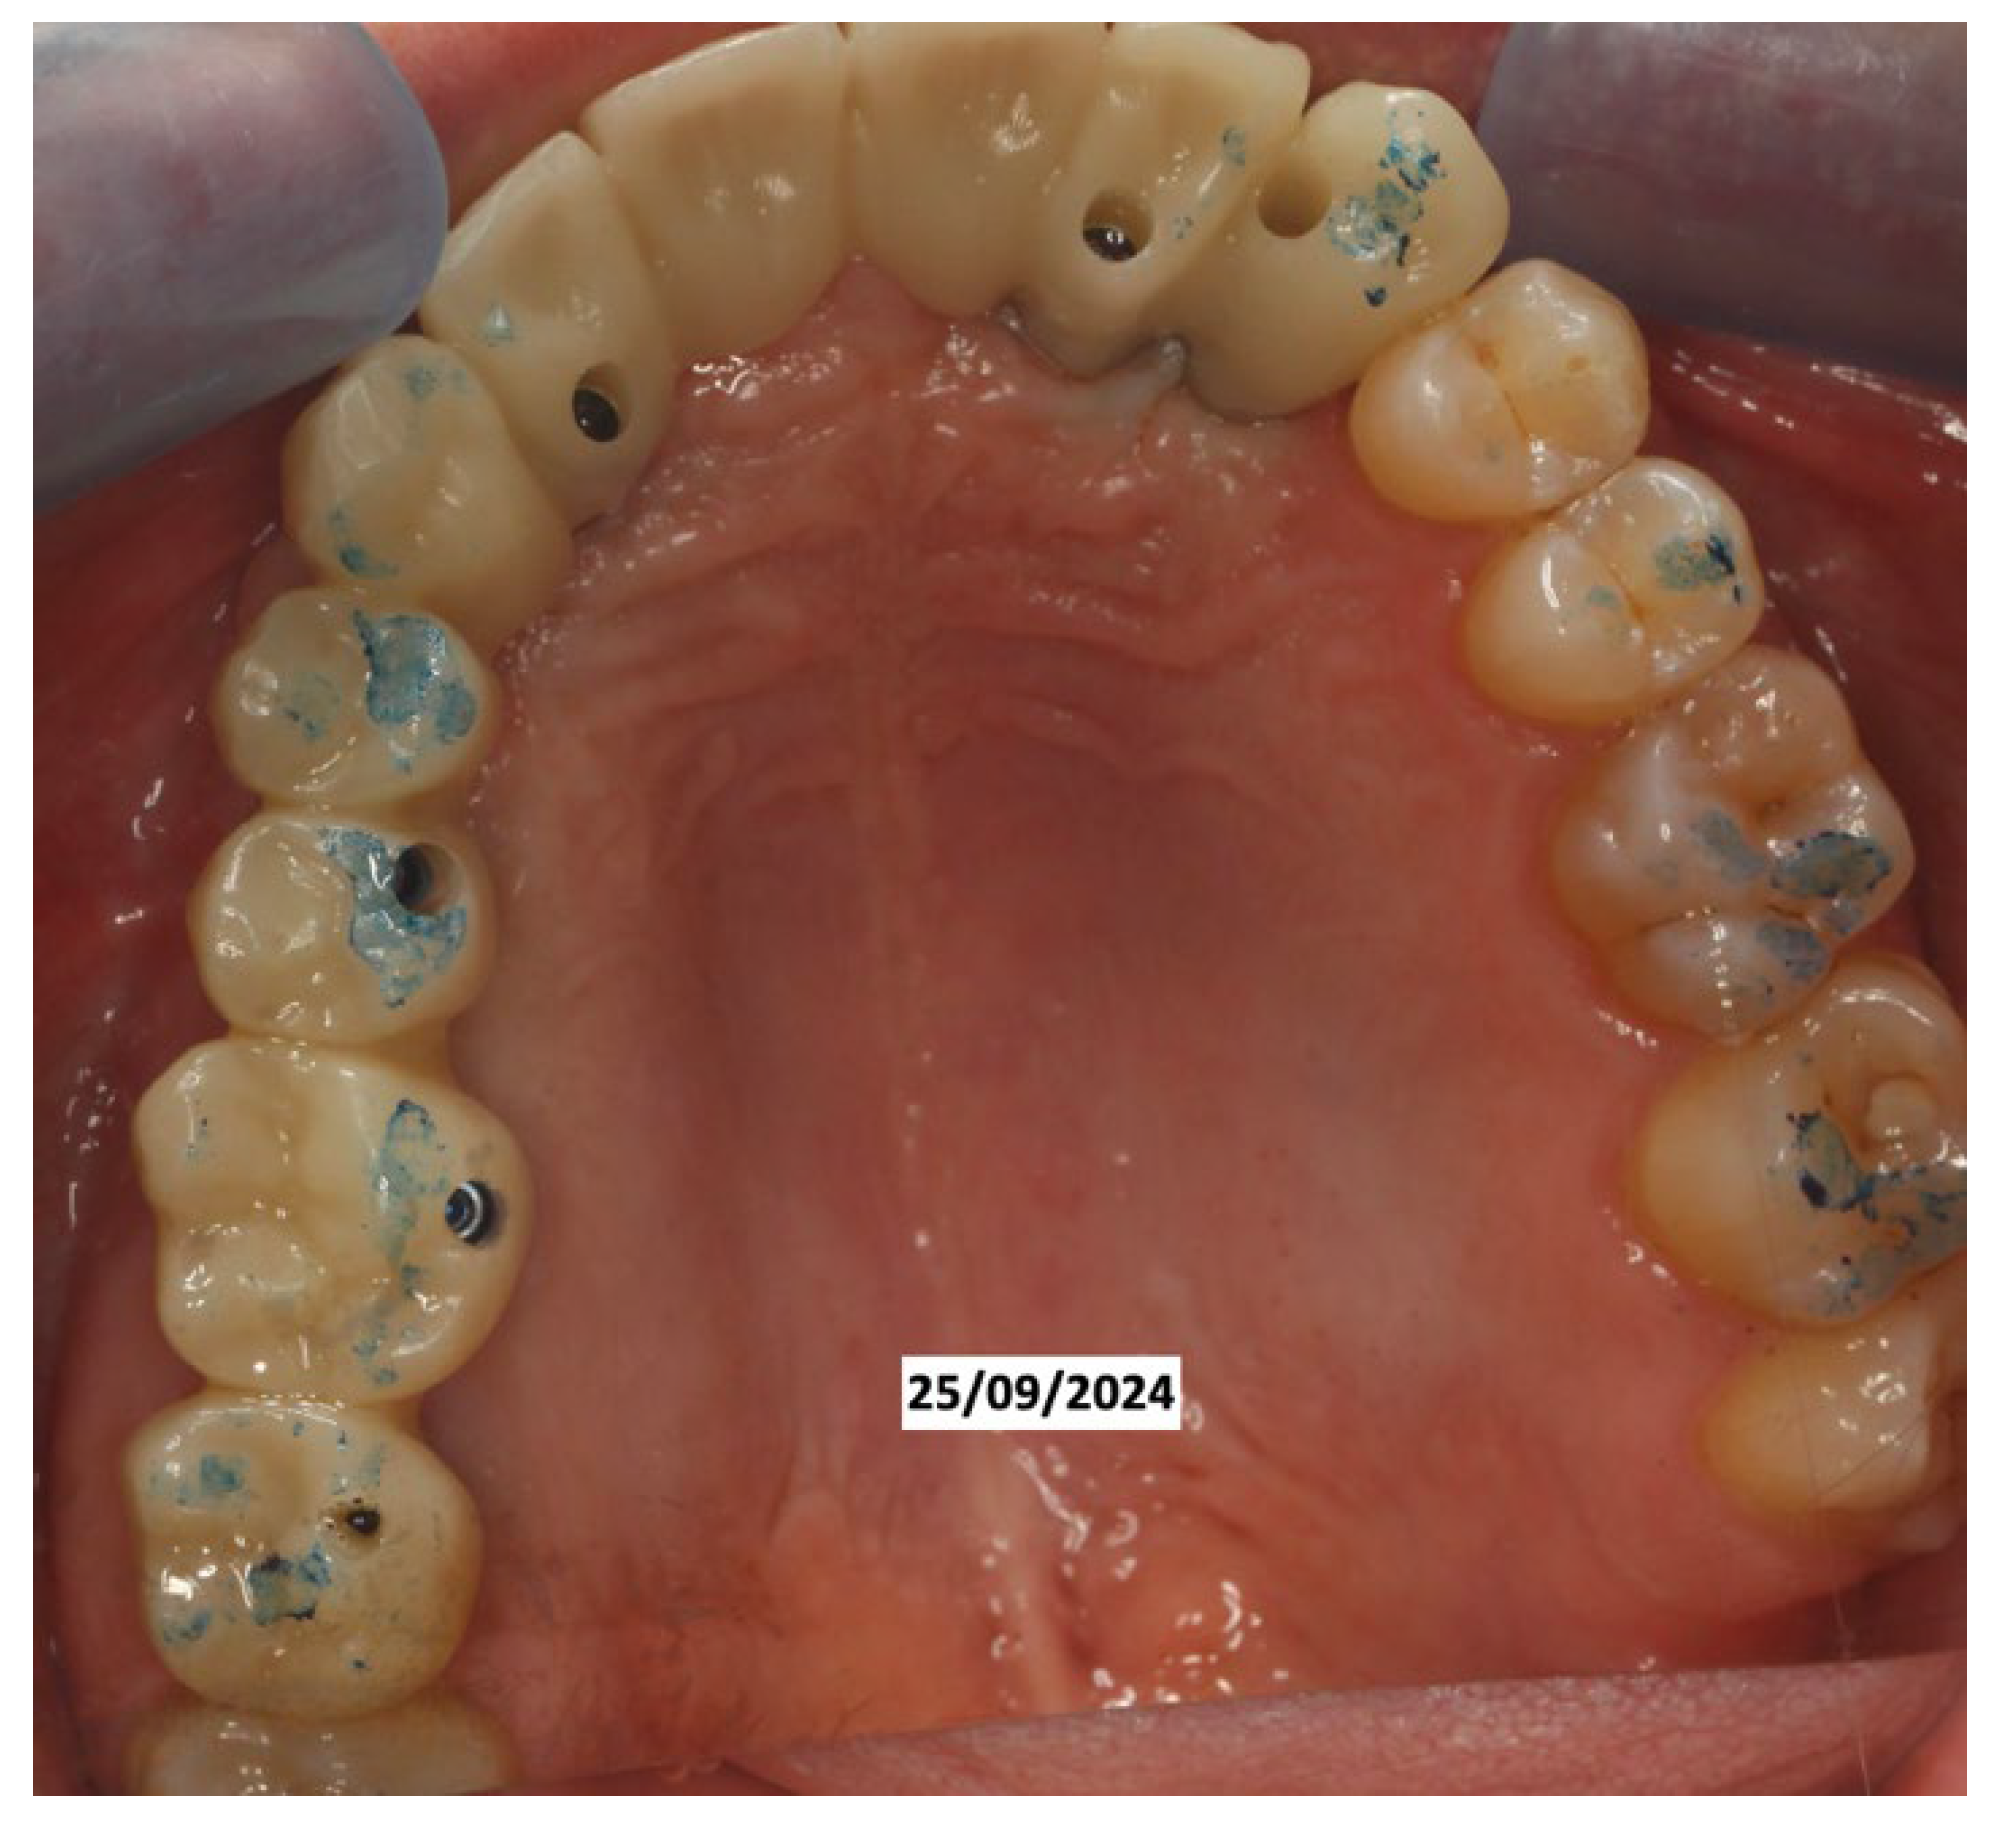

It was decided to temporarily rehabilitate the edentulism with a fixed partial denture after preparing 23-12-13 (Figure 4), keeping the adjacent teeth under observation but with a slight radiolucency already present.

Figure 4. Fixed partial denture after preparing 23-12-13.

In June 2024, the implants were inserted in areas 16 and 17. Three months after the insertion of the last implants in 16-17 (4.2 × 10 mm and 4.2 × 8 mm, Biotech Dental, Allée de Craponne, Salon de Provence, France), it was possible to proceed with the digital impression-taking to proceed with a temporary prosthesis in PMMA (Figure 9) after a radiographic control (Figure 10).